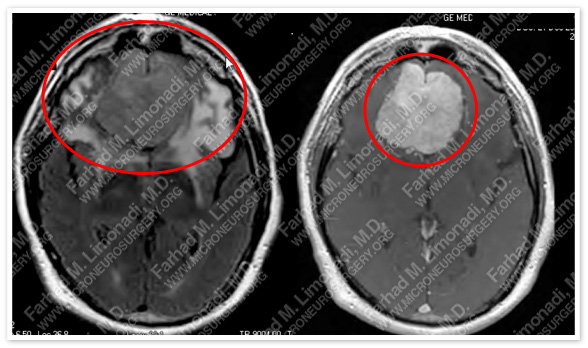

Imaging

MRI scan of the patient’s brain shows a large olfactory groove tumor.

MRI shows significant vasogenic edema around this tumor that occupies a large volume of his brain.